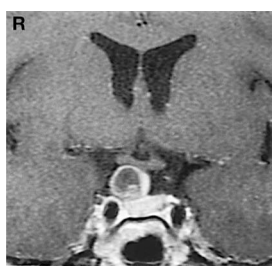

CT和MR检查结果显示,我的右侧鞍上区有一个约2厘米的病灶。这个肿瘤不仅紧贴着垂体柄,还向上突入了第三脑室的底部(图1)。医生初步判断,这可能是颅咽管瘤或垂体腺瘤。

图1:入院时磁共振成像:可见一囊性病灶与垂体柄紧贴,囊壁及内部实性部分呈轻度强化;蝶鞍内垂体形态正常,鞍隔呈低信号带位于肿瘤与垂体之间,二者之间未见连续性。